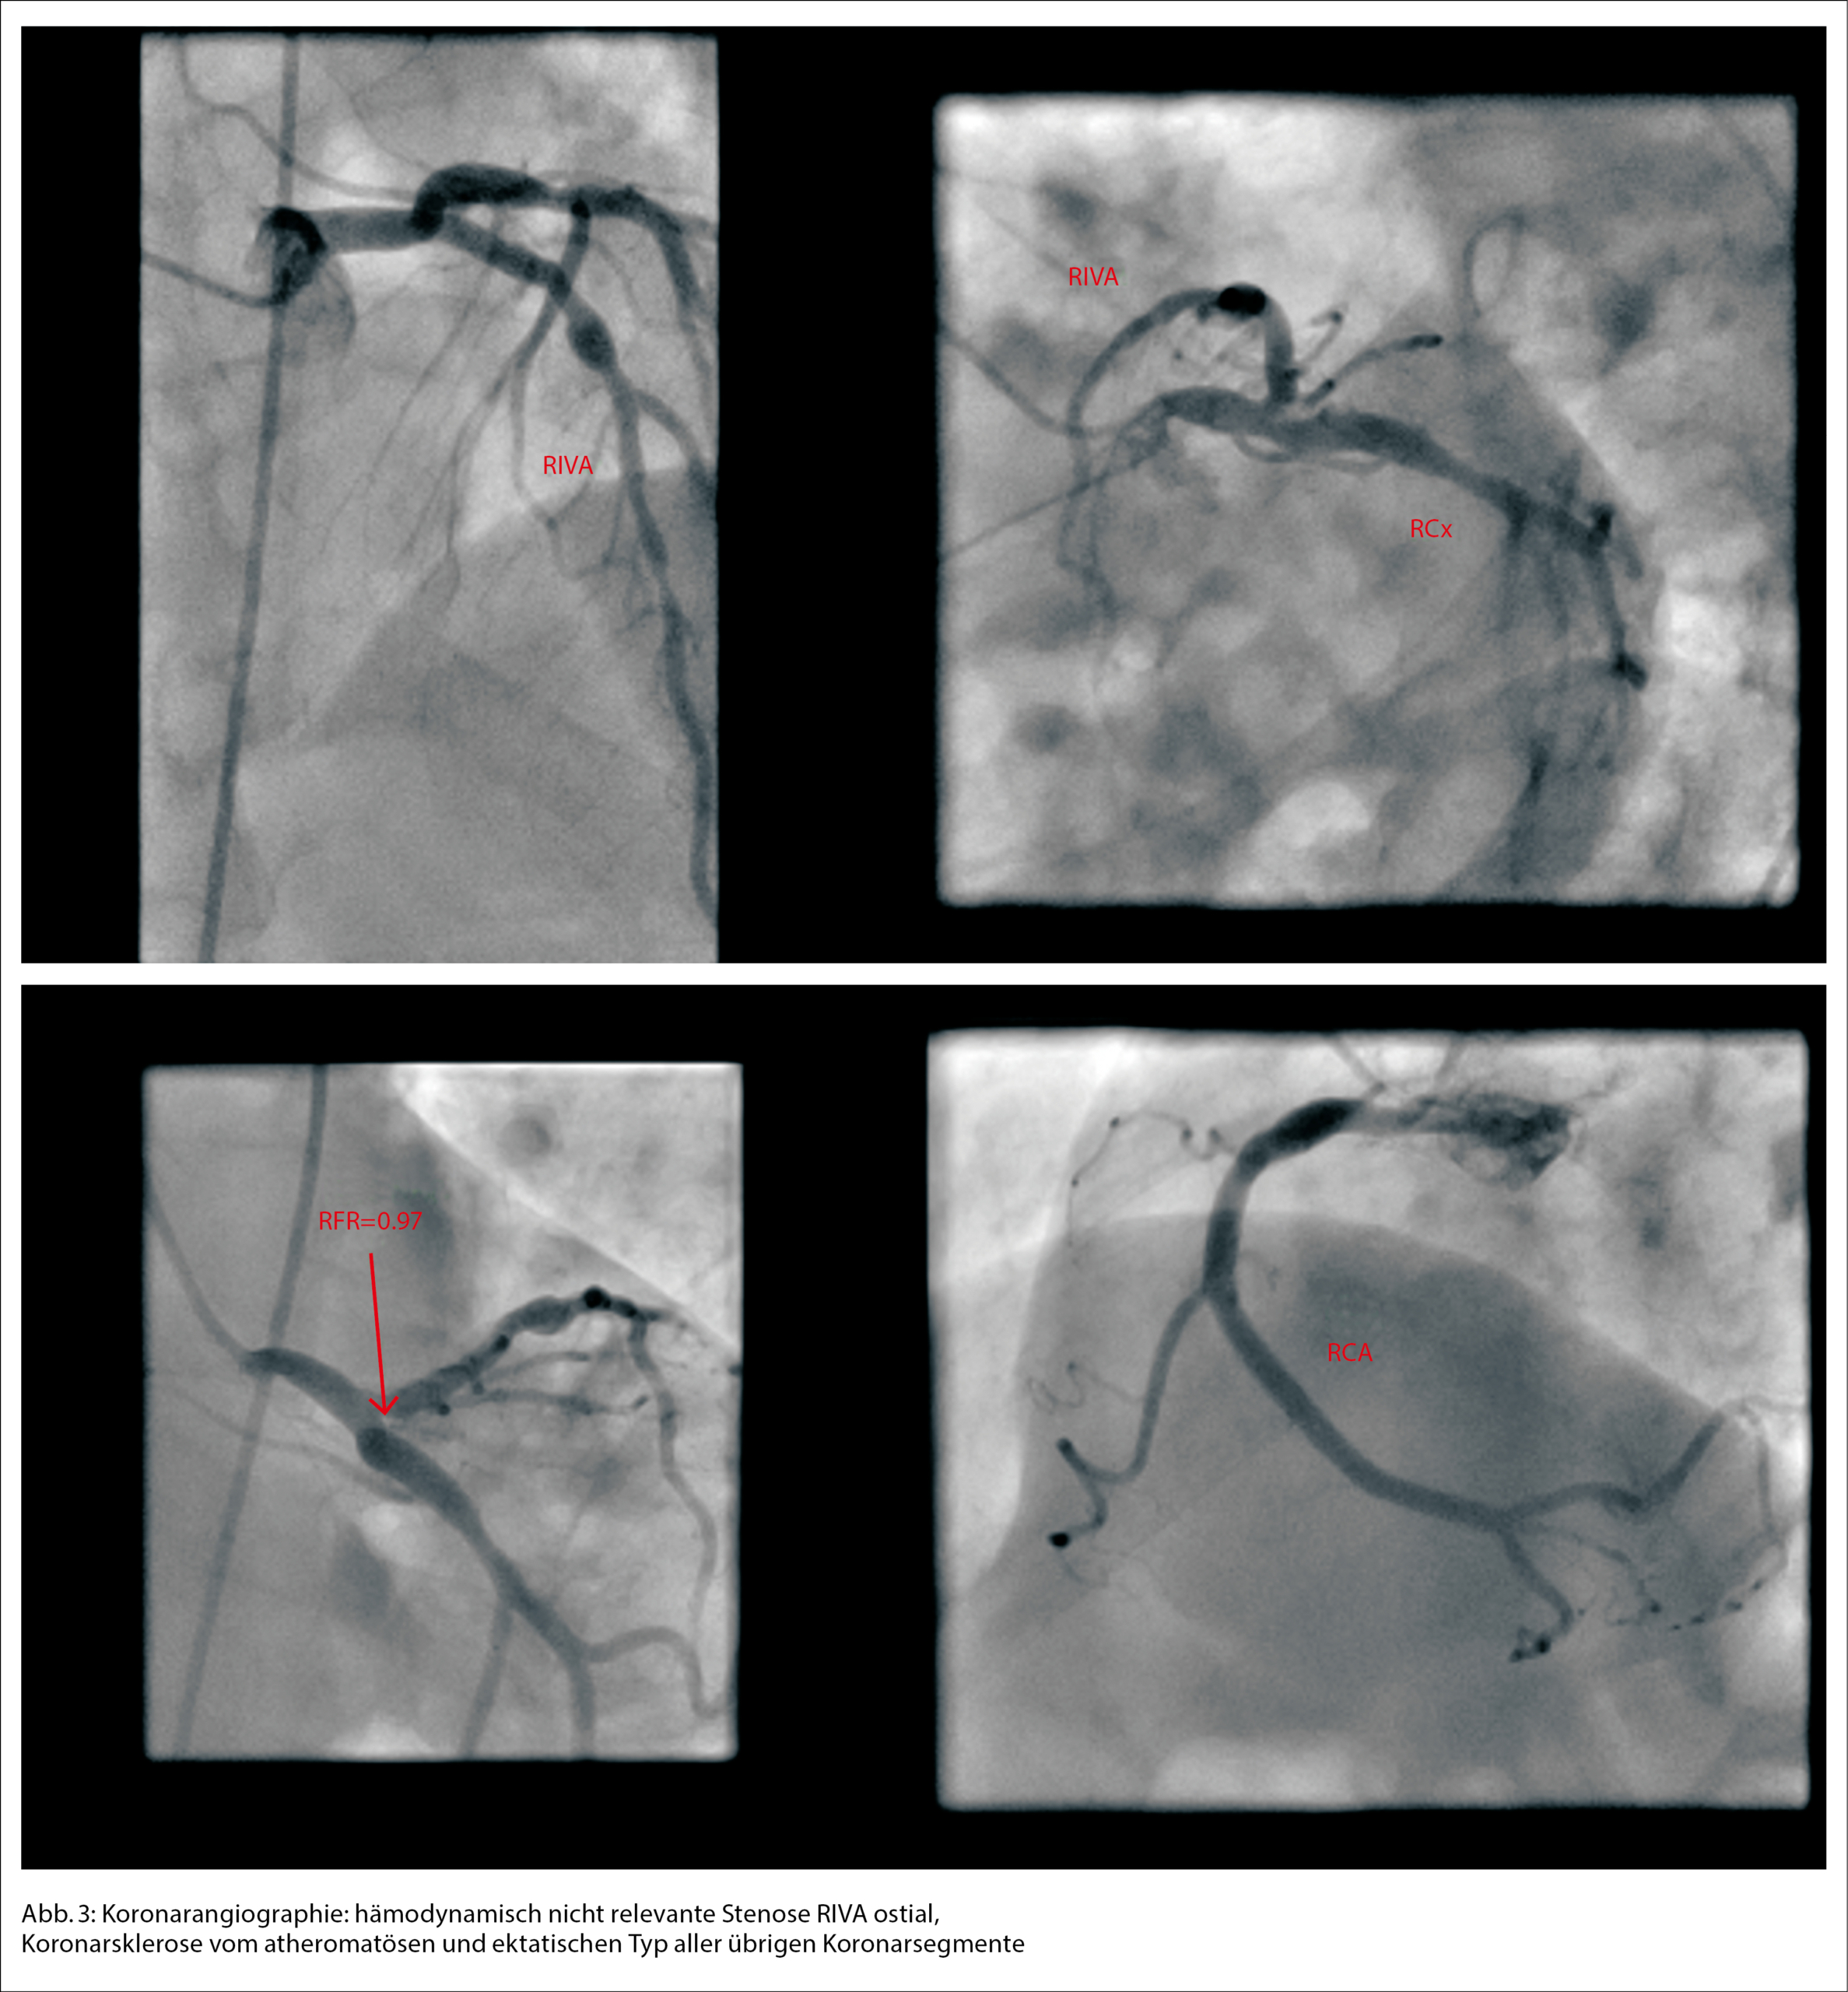

Die Patientin wurde zur weiteren Überwachung auf unsere Intermediate Care Station aufgenommen. In den folgenden Laborkontrollen stieg das kardiale Tro­ponin T deutlich an, was uns veranlasste, unser kardiologisches Team hinzuziehen, da wir ein akutes Koronarsyndrom befürchteten. Die Echokardiographie ergab eine normale Ejektionsfraktion und keinen Hinweis auf Wandbewegungsstörungen. In der Koronarangiographie imponierten die Koronargefässe mit lediglich einer moderaten Koronarsklerose ohne Stenosierung (Abb. 3). In Verbindung mit dem Hauptstamm-EKG wurde ein Koronarspasmus durch die Adrenalingaben postuliert, es zeigten sich in der Koronarangiographie jedoch keine Hinweise für eine höhere Spasmusneigung. Während des Krankenhausaufenthalts zeigten die Folge-EKGs eine Verbesserung der ST-Streckenveränderungen und schliesslich eine Normalisierung.